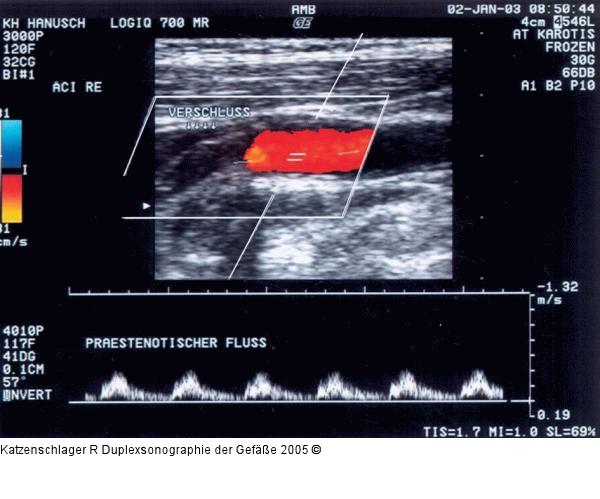

Abbildung 9: Duplexsonographie - Karotis Verschluß der ACI durch einen echoarmen, eher weichen Thrombus |

Abbildung 9: Duplexsonographie - Karotis

Verschluß der ACI durch einen echoarmen, eher weichen Thrombus |